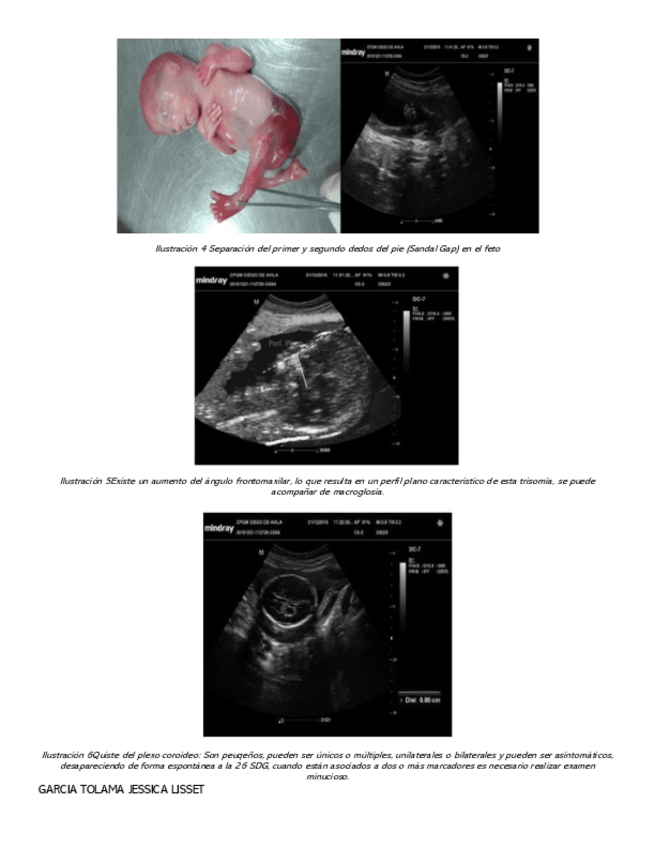

He publicado nuevos apuntes de 8º Obstetricia: SIGNOS-US-EN-EMBARAZO.pdf